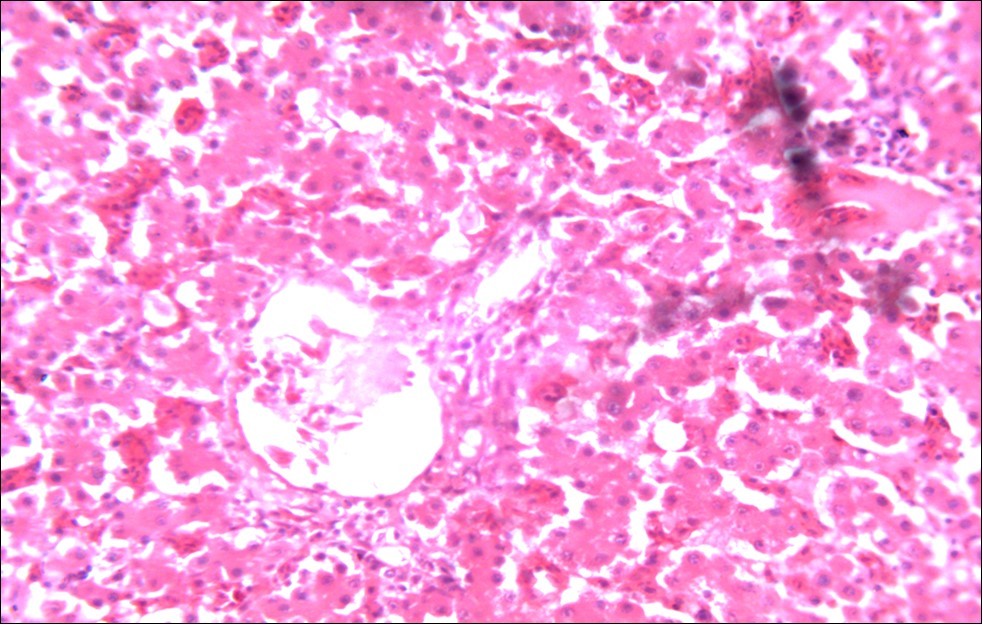

Figure 5.Photomicrograph of caecum of chick administered 20000 Oocysts of Eimeria tenella and treated with NeemAzal® Oil showing generalized degeneration of the caecal glands (d), moderate Ocysts presence (o) with fibrosis (f) X250 (H & E).

In this study, the reduction in oocyst count observed in the treated group was compared with amprolium could be attributed to the presence of a bioactive compounds azadiractin A which is known to bind membrane cholesterol, altering the integrity of the parasite membrane, resulting in loss of homeostasis and eventual death of the parasite 29]. Also, limonoids contained in NeemAzal® inhibit protein digestion and uptake of vitamins and minerals by the parasites in the gut 17. This action results in impaired nutrient utilization, reduced growth, and multiplication of the parasite which could contribute to the reduced oocyst count observed. Extracts of neem and mahogany when used individually have been reported to reduce oocyst count in avian coccidiosis 11,12. The observed reduction in oocyst count and the significant increase in weight gain of the birds when treated with NeemAzal®, as compared with the negative control group could probably be due to the inhibition of inflammation in the intestinal mucosa which is suggestive of an increased nutrient absorption across the intestinal wall and enhanced feed conversion ratio compared to the negative control this is in agreement with reports by Nwosu et al.12 and Biu et al.11 who also reported an increased weight gain and feed conversion ratio in birds treated with only Khaya senegalensis extracts and Azardiractaindica, respectively. The observed increase in RBC and haemoglobin concentration is indicative of the erythropoieticability of the NeemAzal®, which is beneficial since the Eimeria parasite in the epithelia of the intestines causes bloody diarrhoea and consequently anaemia (Table 1). This finding is in consonance with 15 who reported an anti-anaemic effect of Khaya Senegalensis on phenyl hydrazine-induced anaemia in rats. Neem has been shown to possess anti-anaemic properties in rats 14. The significant increase in mean weight gain in treated birds when compared to the negative control is possibly due to the inhibition of inflammation in the intestinal mucosa which is suggestive of an increased nutrient absorption across the intestinal wall and enhanced feed conversion ratio compared to the negative control. Nwosu et al.12 and Biu et al.11 reported an increased weight gain and feed conversion ratio in birds treated with only Khaya Senegalensis andAzadiractaindica extracts, respectively. In a similar study, Neem acts like toltrazuril exhibiting anticoccidial. In addition, exposure of broiler chickens to 20000 Oocysts of Eimeria tenellacaused generalized degeneration of the caecal glands with massive Oocysts and gametocyts within the caecal glands with fibrosis (Figure 3, Figure 4 & Figure 5), however, broiler chickens treated with NeemAzal® post exposure to 20000 Oocysts of Eimeria tenella, shows equal numbers of caecal tissues with non-observable histopathological lesions (Figure 4), possibly due to the antioxidant and anti-coccidian effects of NeemAzal®. The exact mechanism of action of neem against coccidian parasites is unknown, but a report by the National Research Council 1992 30, suggested that aqueous neem leaf extract, when taken orally, produces an increase in red cells, white blood cells and lymphocyte counts thus enhancing the cellular immune response, increasing antibody production and so most pathogens can be removed before they cause the symptoms associated with disease this was in agreement with this study as seen in Table a remarkable increase of the RBCs.

In addition, the generalized degeneration of the caecal glands, moderate numbers of gametocytes within the glandular regions with fibrosis which underscores reparative process in response to injury evoked by coccidiosis in the chicks which was perhaps brought about by the antioxidant and chemotherapeutic effect of NeemAzal®. The observed increase in RBC and hemoglobin concentration (Table 1) is indicative of the erythropoieticability of NeemAzal®, which is beneficial since the Eimeria parasite in the epithelia of the intestines causes bloody diarrhea and consequently anaemia. This finding is in consonance with 15 who reported an anti-anaemic effect of Khaya senegalensis on phenyl hydrazine-induced anaemia in rats. If the results of this study are juxtaposed with the results of the previous studies on potent antioxidant, hepatoprotective and mitigative role of methanolic extracts of Azadirachtaindica,in both natural and experimental infection with Eimeria species and can be deduced that, NeemAzal® could be said to be a potent antioxidant, chemotherapeutic and tissue protective agent. This study also answered a question on further study advocated to determine the maximum safe levels of neem supplementation because the higher doses, due to its bitterness, may show adverse effects on feed intake which will change the performance parameters of birds (Figure 6 and Figure 7) . Light microscopic inspection of hematoxylin and eosin-stained sections revealed that the epithelial cells of the Cecum were infected by E. tenella(Figure 3 and Figure 4). The results of the safety study showed that exposure of chickens to NeemAzal® at 200mg/kg body weight did not alter the histoarchitecture of liver and kidney (Figure 6 & Figure 7) which is similar to the work conducted in the same environment by a group of Scientists 34. It is therefore recommended that NeemAzal® could be used as a coccidiostat to replace the expensive anti-coccidiostats in the market.